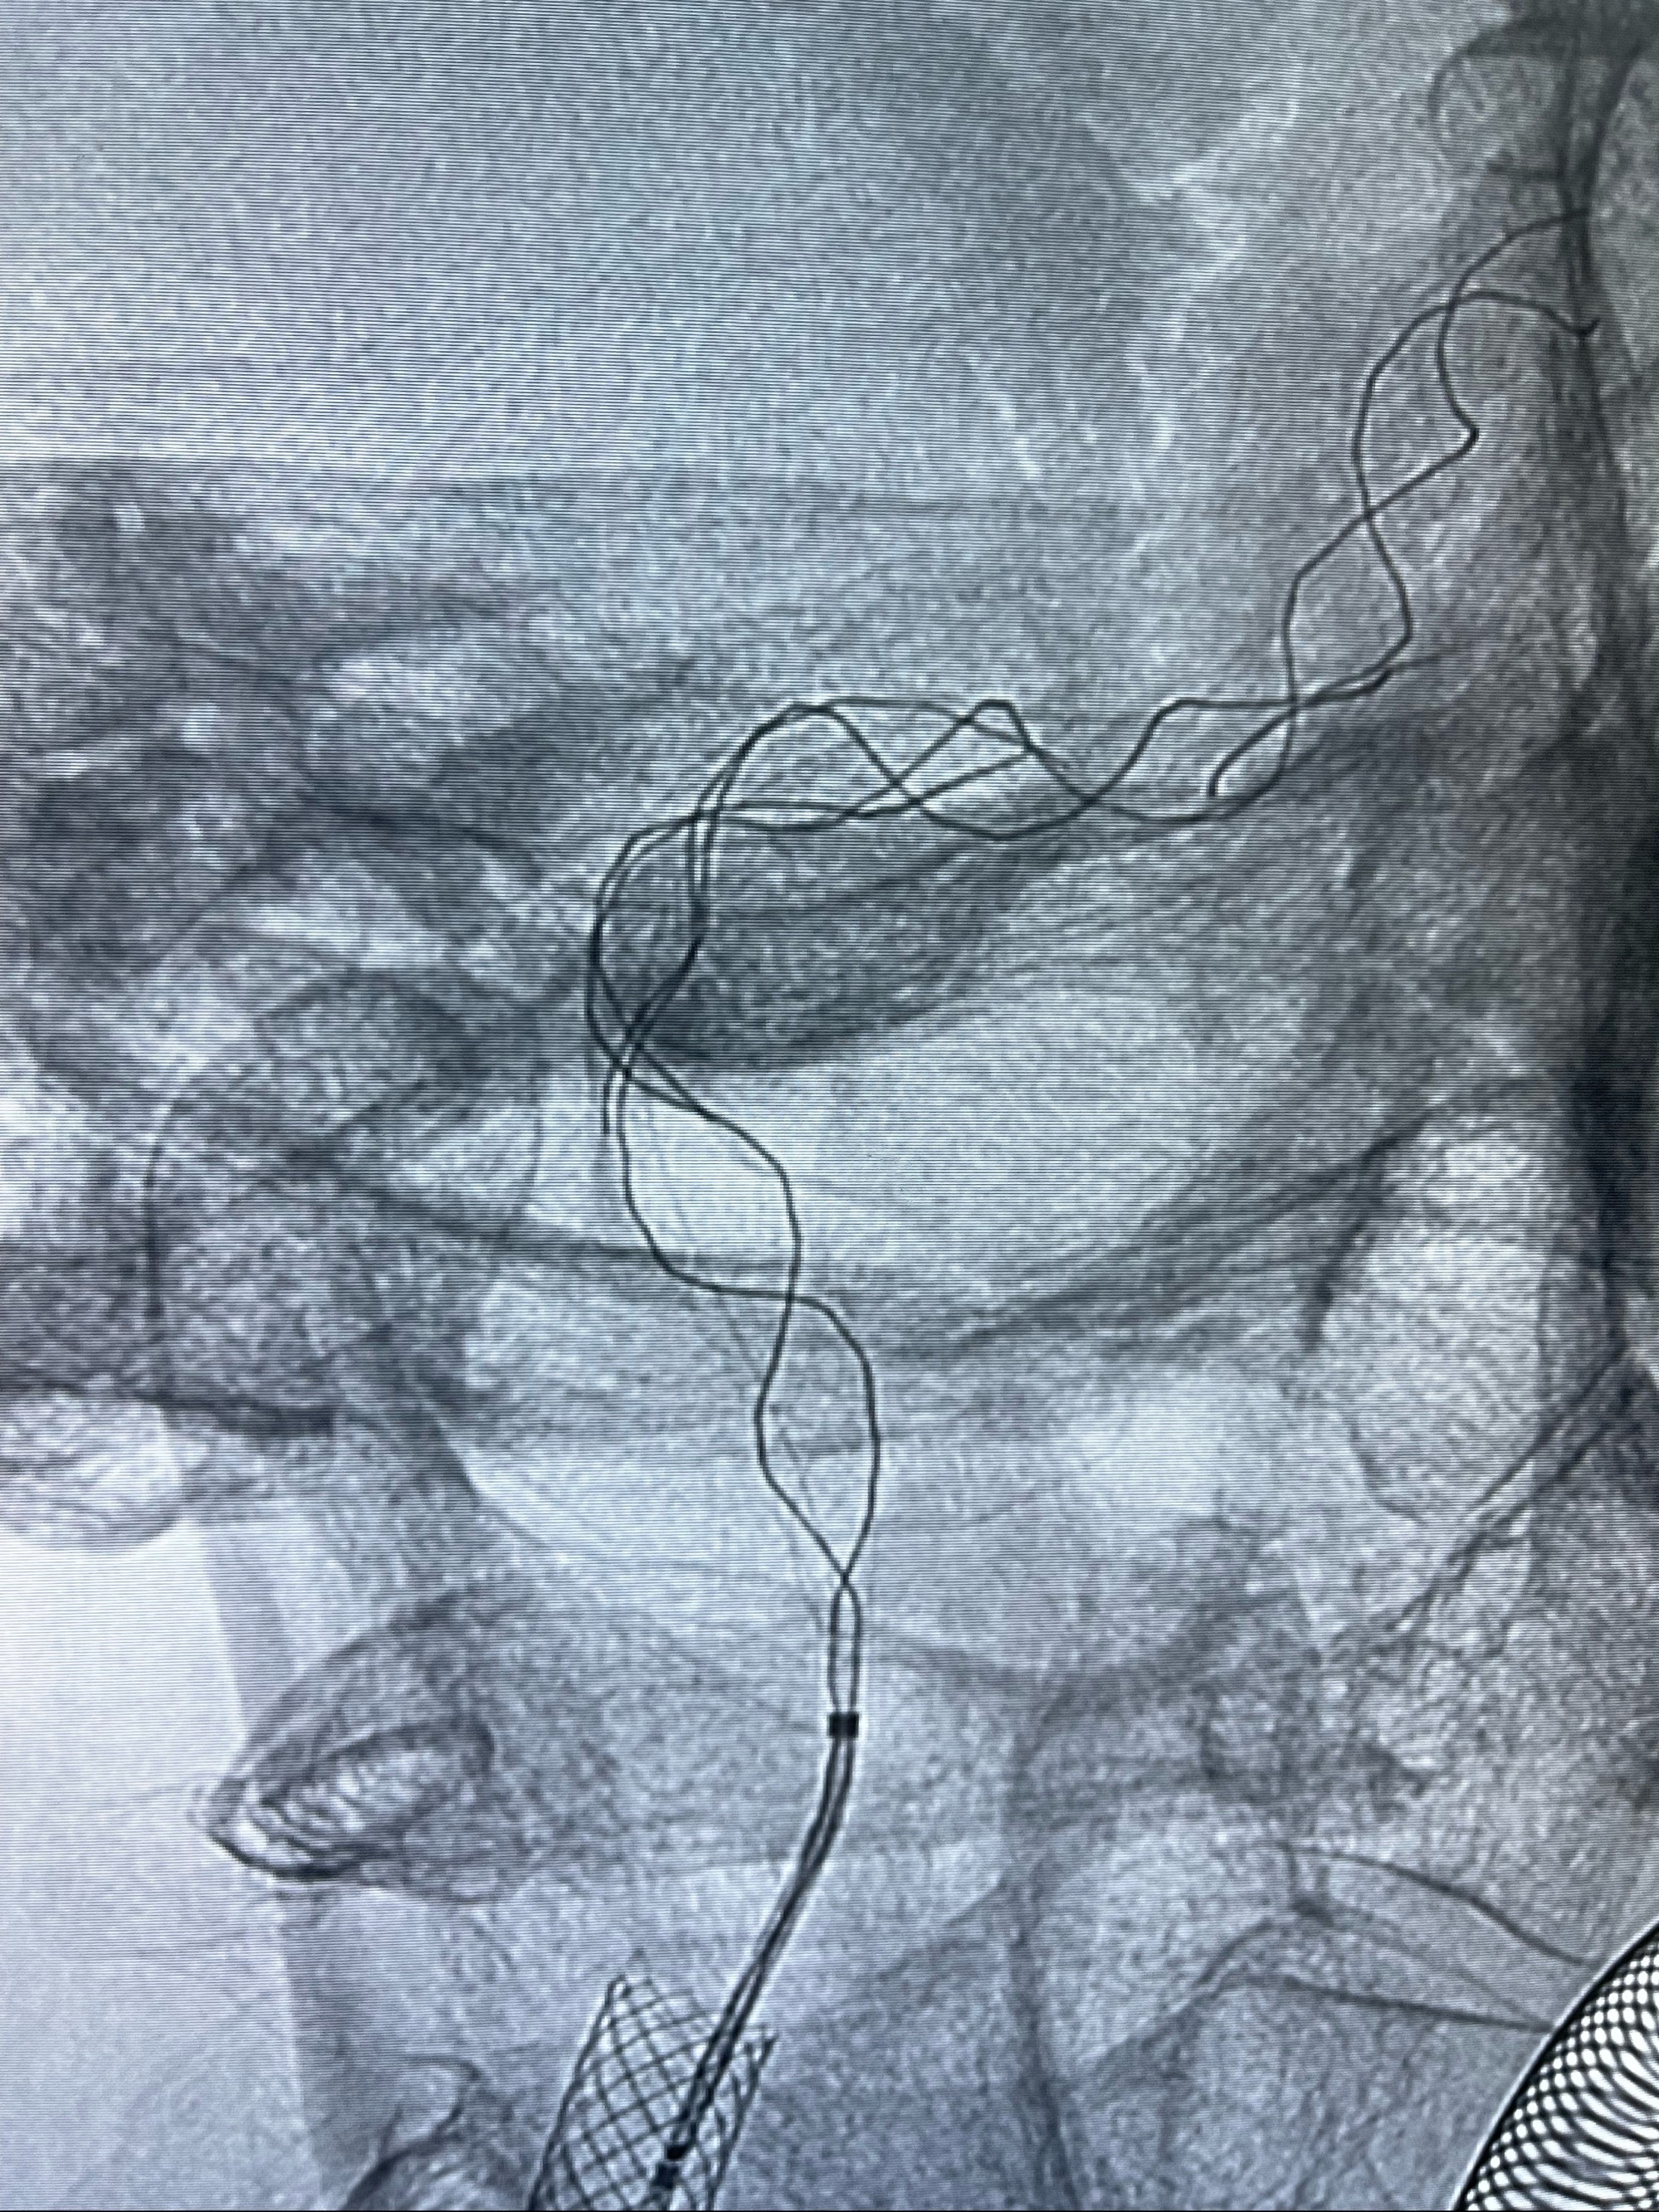

双抗准备后于2023-07-13在全麻下行右侧颈内动脉功能保护

088NeuroMAX100cm长鞘在125cmMPA及黑泥鳅导丝引导下超选择性插入右侧颈内动脉支架内

经导引导管造影显示支架远端颈内动脉不规则狭窄伴局部充盈缺损,同时行全身肝素化5ml

路径图下4-20mm球囊在导丝引导下超选择性至狭窄段,以6-8个大气压扩张,持续30s

泄除球囊造影显示局部管腔扩张佳

后移球囊至颈段狭窄段,以8-12个大气压扩张,持续30s后泄除球囊

即刻造影显示狭窄扩张佳

重新行“路径图”,支架导管在微导丝引导下超选择性插入至右侧颈内动脉眼段,4.5-50mmLeo支架释放,远心端位于海绵窦段,近心端位于岩骨段狭窄段以近

即刻造影显示支架贴壁佳

路径图下,5.5-50mmLeo支架导管在微导丝引导下超选择性插入远段Leo支架内

两枚支架部分重叠

多次确认支架位置及打开贴壁情况

支架完全打开,近心端位于原颈动脉支架远心端内